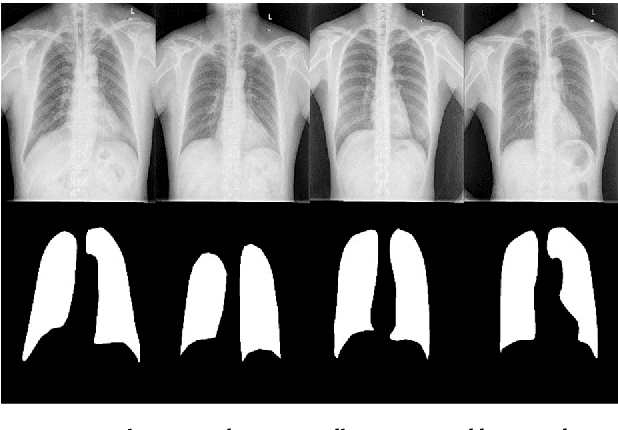

Abstract:Chest X-ray (CXR) is a low-cost medical imaging technique. It is a common procedure for the identification of many respiratory diseases compared to MRI, CT, and PET scans. This paper presents the use of generative adversarial networks (GAN) to perform the task of lung segmentation on a given CXR. GANs are popular to generate realistic data by learning the mapping from one domain to another. In our work, the generator of the GAN is trained to generate a segmented mask of a given input CXR. The discriminator distinguishes between a ground truth and the generated mask, and updates the generator through the adversarial loss measure. The objective is to generate masks for the input CXR, which are as realistic as possible compared to the ground truth masks. The model is trained and evaluated using four different discriminators referred to as D1, D2, D3, and D4, respectively. Experimental results on three different CXR datasets reveal that the proposed model is able to achieve a dice-score of 0.9740, and IOU score of 0.943, which are better than other reported state-of-the art results.